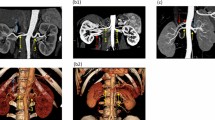

After RDN, in two patients a new renal artery stenosis was observed (lumen reduction in both cases 25–49%) and in one patient there was progression of a pre-existing lumen reduction (from <25% to 50–74%). Two of the three patients with vascular changes were treated with the Symplicity™ catheter and one with the EnligHTN™ multi-electrode system.

To assess the possible relationship between vascular changes and the radiofrequency ablations, we analysed the DSA images performed during RDN. In only one of the three patients with vascular changes after RDN we could conclude that ablations were applied near the location where on the follow-up MRA a new stenosis was observed (Fig. 1). Furthermore, we concluded that findings on the pre-procedural MRA corresponded to the DSA images.

Table 4 presents the individual characteristics of the patients with newly observed or progressed renal artery stenosis. Only one of the three patients showed a marked decrease in BP. No other clinical signs (i.e. impaired kidney function) of renal artery stenosis were reported. Also in these patients, kidney length did not change after RDN.

Based on the evaluation of the procedural angiographies, we concluded that only in one patient the newly observed stenosis was located in an ablated area. A relationship with the procedure could therefore not be excluded. In the other two patients, there was no reason to believe that the new or progressed lumen reduction after RDN may have been a result of the ablations (very proximal stenosis and more distally ablated). The natural history of renal vascular anomalies within 1 year in hypertensive patients who had no stenosis at baseline is not often investigated. In 1998, Caps and co-workers reported a cumulative incidence of progression to ≥60% stenosis of at least 5% after 1 year in patients who were initially wrongly suspected of having atherosclerotic renal artery stenosis (investigated by duplex ultrasonography) [32]. The cumulative incidence of progression in patients with pre-existing stenosis was almost five times higher. Two other studies showed that in a population of resistant hypertensive patients with relatively high vascular morbidity, occurrence or progression of renal artery atherosclerosis is very likely [33, 34]. For a correct interpretation of the currently presented results, a comparison with (randomized) control patients and differentiation between atherosclerosis and other causes of renal artery stenosis would be useful. However, this differentiation is radiologically challenging.